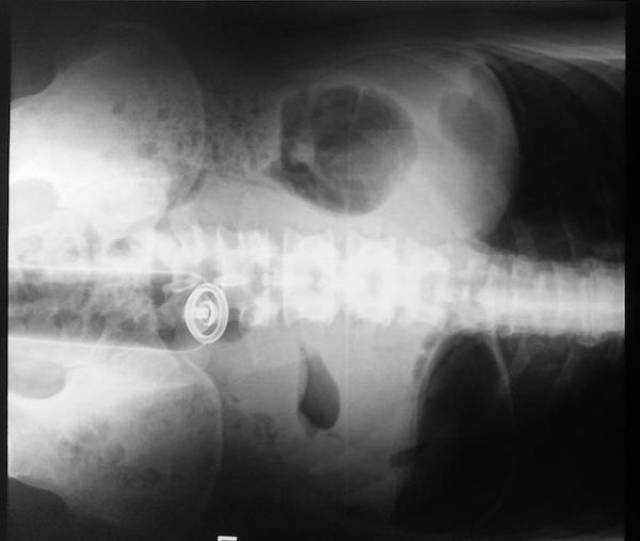

Mercury from a shattered thermometer.